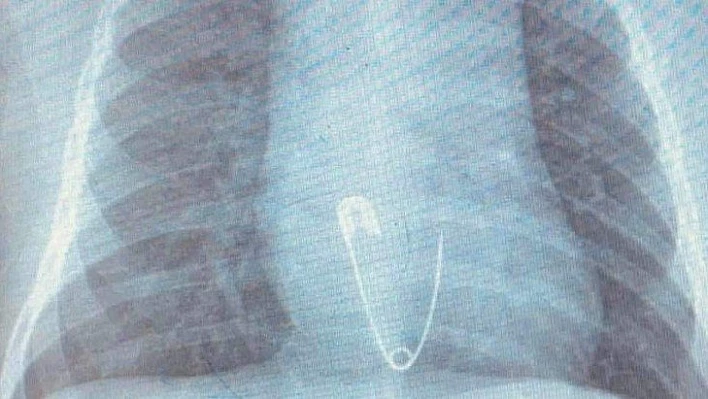

Hastanın Diyarbakır’dan Elazığ’a geldiğini belirten Prof. Dr. Yaşar Doğan, “Hastayı kabul ettik, 5 aylık bir hasta. Bize gelmeden önce üzerinde bulunan nazar boncuğunu çengelli iğne ile birlikte ağzına götürmüş. Aile de fark edince müdahale etmiş, ağzındaki nazar boncuğunu çıkarmış fakat o esnada çengelli iğne yemek borusuna kaçmış. Hasta geldiği zaman çektiğimiz röntgende çengelli iğne yemek borusunun alt kısmında takılı vaziyetteydi. Hastaya 15 dakikalık sedasyon altında işlem yapıldı, endoskopi ile parça çıkarıldı. Hasta şu anda gayet iyi. Biraz sonra da evlerine göndereceğiz” dedi.